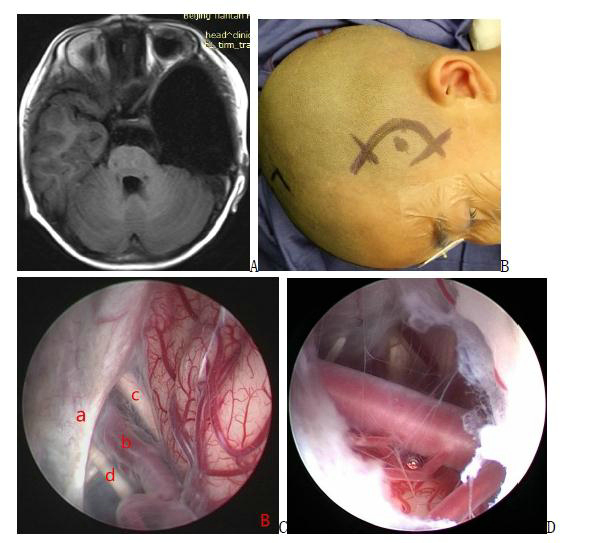

Neurosurgical Oncology Ward 3Neurosurgical Oncology Ward 3 (Middle-line skull base tumors and neuroendoscopy) Specialized features The Neurosurgical Oncology Ward 3 is characterized by the clinical application of neuroendoscopic technology. The annual number of neuroendoscopic surgeries exceeds 1200, and the quantity and quality of neuroendoscopic surgeries are leading domestically and internatio…